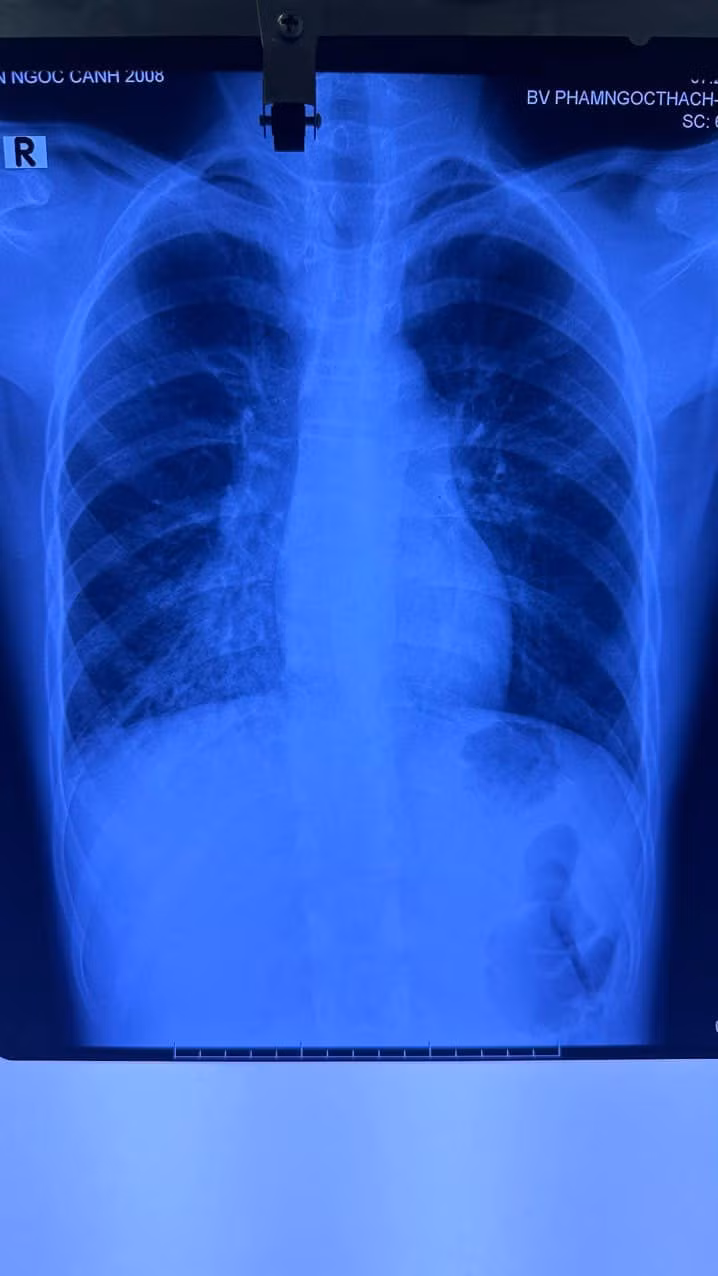

Cách nay hơn 1 tháng, bé bỗng nhiên ho nhiều hơn và người nhà đưa bé đến khám tại nhiều bệnh viện chuyên khoa tại TP HCM, chụp Xquang, CT ngực, thậm chí điều trị lao nhưng tình trạng vẫn không cải thiện, bé ho nhiều, XQ phổi không giảm.

Thời gian sau bé về quê khám tại BV chuyên lao và bệnh phổi Bình Định, tại đây chụp CT Scan phổi lại nghi dị vật đường thở nên người nhà xin chuyển BV Nhi Đồng 1 nội soi đường thở.

| Một số hình ảnh phim Xquang, CT ngực, hình qua nội soi đường thở và dị vật gắp được |